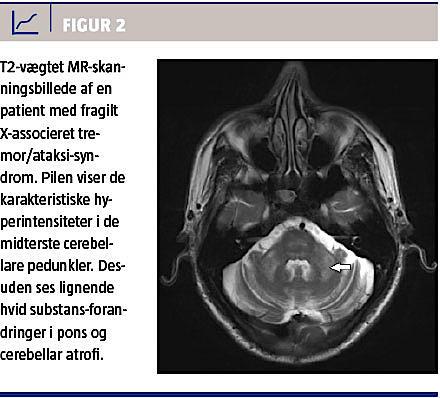

MR-skanning er en vigtig del af FXTAS-diagnosticeringen, idet der typisk ses cerebral og cerebellar atrofi og som et relativt specifikt fund desuden hvid substans-forandringer [16] i de midterste cerebellare pedunkler (MCP) hos ca. 60% og 13% af hhv. mænd og kvinder [13, 16]. Figur 2 er et MR-billede med MCP-tegn. I et nyligt publiceret studie fandt man, at øget intensitet i corpus callosum splenium (CCS) forekom lige så hyppigt som MCP ved FXTAS, og forfatterne foreslog, at CCS skulle indgå som et nyt radiologisk kriterium (Tabel 1) [15].

De typiske forandringer er også påvist ved MR-skanning hos asymptomatiske mænd med FMR1-præmutation, hvilket indikerer, at der er tale om en proces, der begynder flere år før, de kliniske symptomerne bliver åbenlyse [17].